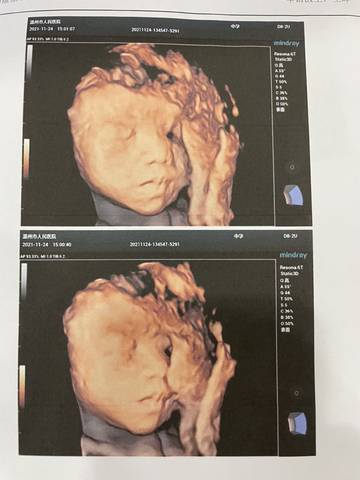

大家帮忙看下是????????还是????????

笑容灿烂的 2021-12-09 22:30

你好,对于宝宝是男孩女孩,怀孕的单子、数据、表现是判断不出来的,等到生下来才是最靠谱的。